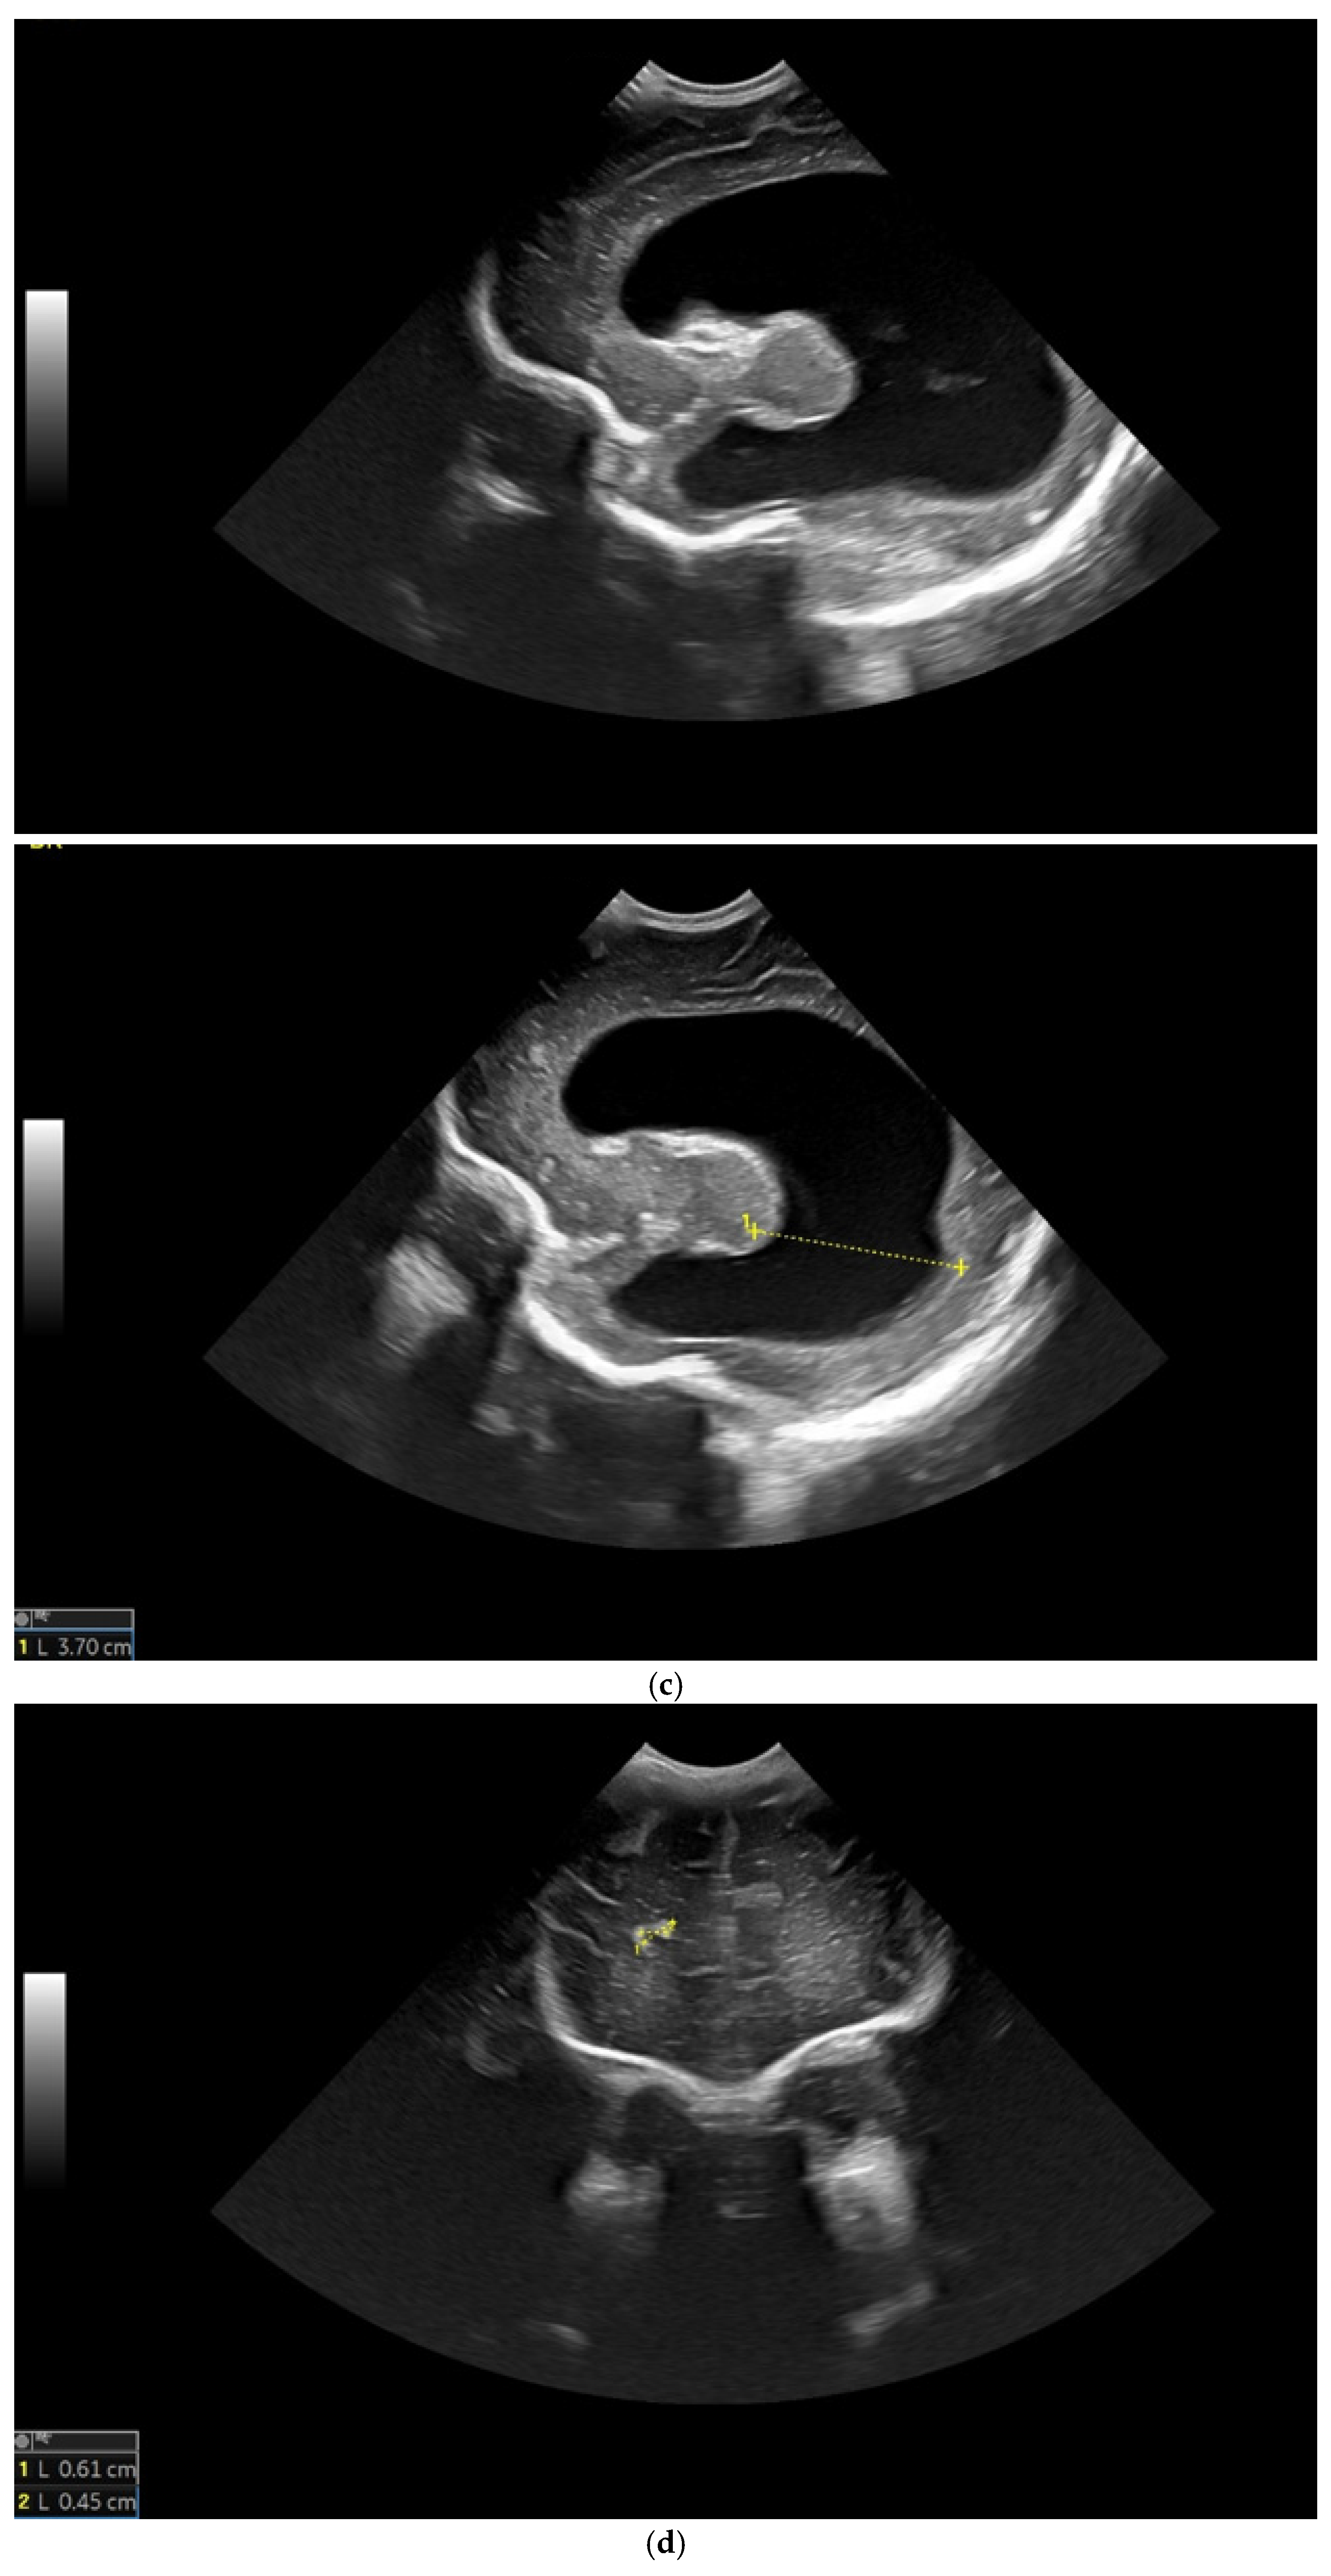

The first CUS was performed 24 h after birth and showed dilation of the third and fourth lateral ventricles, enlargement of the Sylvius aqueduct, and the presence of an arachnoid cyst (Figure 3a–e).

Figure 3.

(a) Cranial ultrasound. Coronal view. Enlargement of the lateral ventricles with hyperechoic and third ventricle dilation. D1, D2—Levine index measurement. D3, D4—anterior horn width measurement. D5—third ventricle (personal image collection). (b) Cranial ultrasound. Sagittal view. Up—left ventricle. D1, D2—lateral ventricle measurements and thalamo-occipital horn width. Down—right ventricle. D1, D2—lateral ventricle measurements and thalamo-occipital horn width (personal image collection). (c) Cranial ultrasound. Sagittal view. Up—enlargement of the third and fourth ventricles. Measurements of the ventricles. Down—measurement of the resistive index (RI) performed on the anterior cerebral artery (ACA) using Doppler flow measurements. RI—0.74 (personal image collection). (d) Cranial ultrasound. Transtemporal view. Yellow arrow—enlargement of the Sylvian aqueduct (personal image collection). (e) Cranial ultrasound. Sagittal view. Yellow arrow—arachnoid cyst posterior to the third ventricle (personal image collection). (f) Cranial ultrasound. Coronal view. Lateral ventricles and third ventricle enlargement. D1, D2—Levine index measurement. D3, D6—right lateral ventricle measurement (anterior horn width). D4, D5—left lateral ventricle measurement (anterior horn width) (personal image collection). (g) Cranial ultrasound. Sagittal view. Left—left ventricle. D1—thalamo-occipital distance measurement. Right—right ventricle. D2—thalamo-occipital distance measurement (personal image collection). (h) Cranial ultrasound. Coronal view. Up—orange arrow—third ventricle. Red arrow—fourth ventricles. Yellow arrow—arachnoid cyst. Down—resistive index measured on the anterior cerebral artery. RI—0.79 (personal image collection). (i) Cranial ultrasound. Transversal view. Up—RI precompression value on the middle cerebral artery performed with Doppler examination. RI—68. Down—RI post-compression value on the middle cerebral artery performed with Doppler examination. RI—0.79 (personal image collection). (j) Cranial ultrasound. Up—coronal view. L1, L2—Levine index measurement of the lateral ventricles. Down—sagittal view. L1, L2—measurement of the thalamo-occipital distance (personal image collection). (k) Cranial ultrasound. Sagittal view. L1, L2—measurement of the third ventricle. L3, L4—measurement of the fourth ventricle. L5, L6—measurement of the arachnoid cyst (personal image collection). (l). Head circumference-for-age. “X” symbols represent the measurements performed from birth and follow-up examinations. Head circumference was still under the curve during follow-up examinations (personal image collection) [28].

The CUS examination performed at 48 h after birth showed increases in the diameters of all ventricles. The resistive index presented an increase as well. The bregmatic fontanelle started bulging. The dimensions of the Sylvian aqueduct were not modified (Figure 3f–h).

The CUS examinations performed at four days and seven days after birth showed stabilization regarding the values of the diameters. The pre- and post-compression values of the resistive index of the middle cerebral artery showed a delta-RI of 0.11 (pre—0.68, post—0.79, Figure 3i).